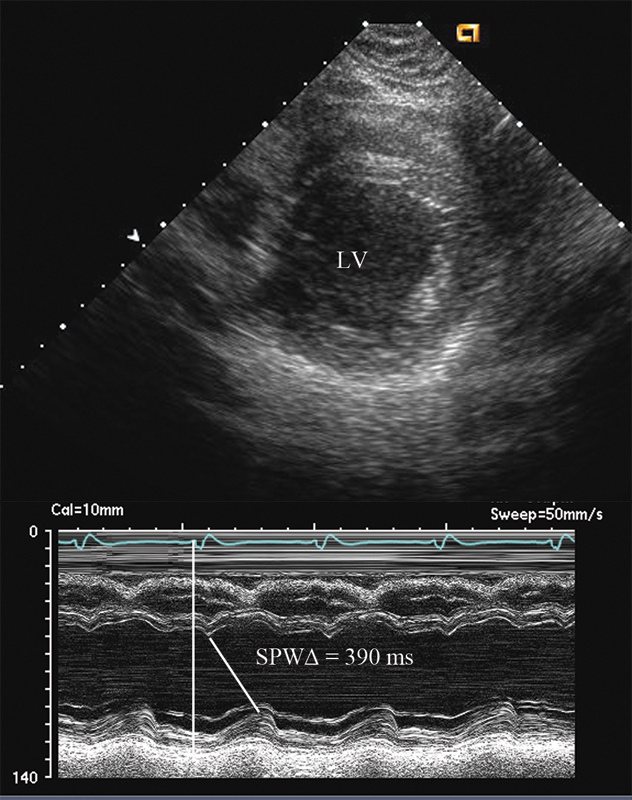

فحوصات تشخيصية لبعض امراض القلب والشرايين التاجية